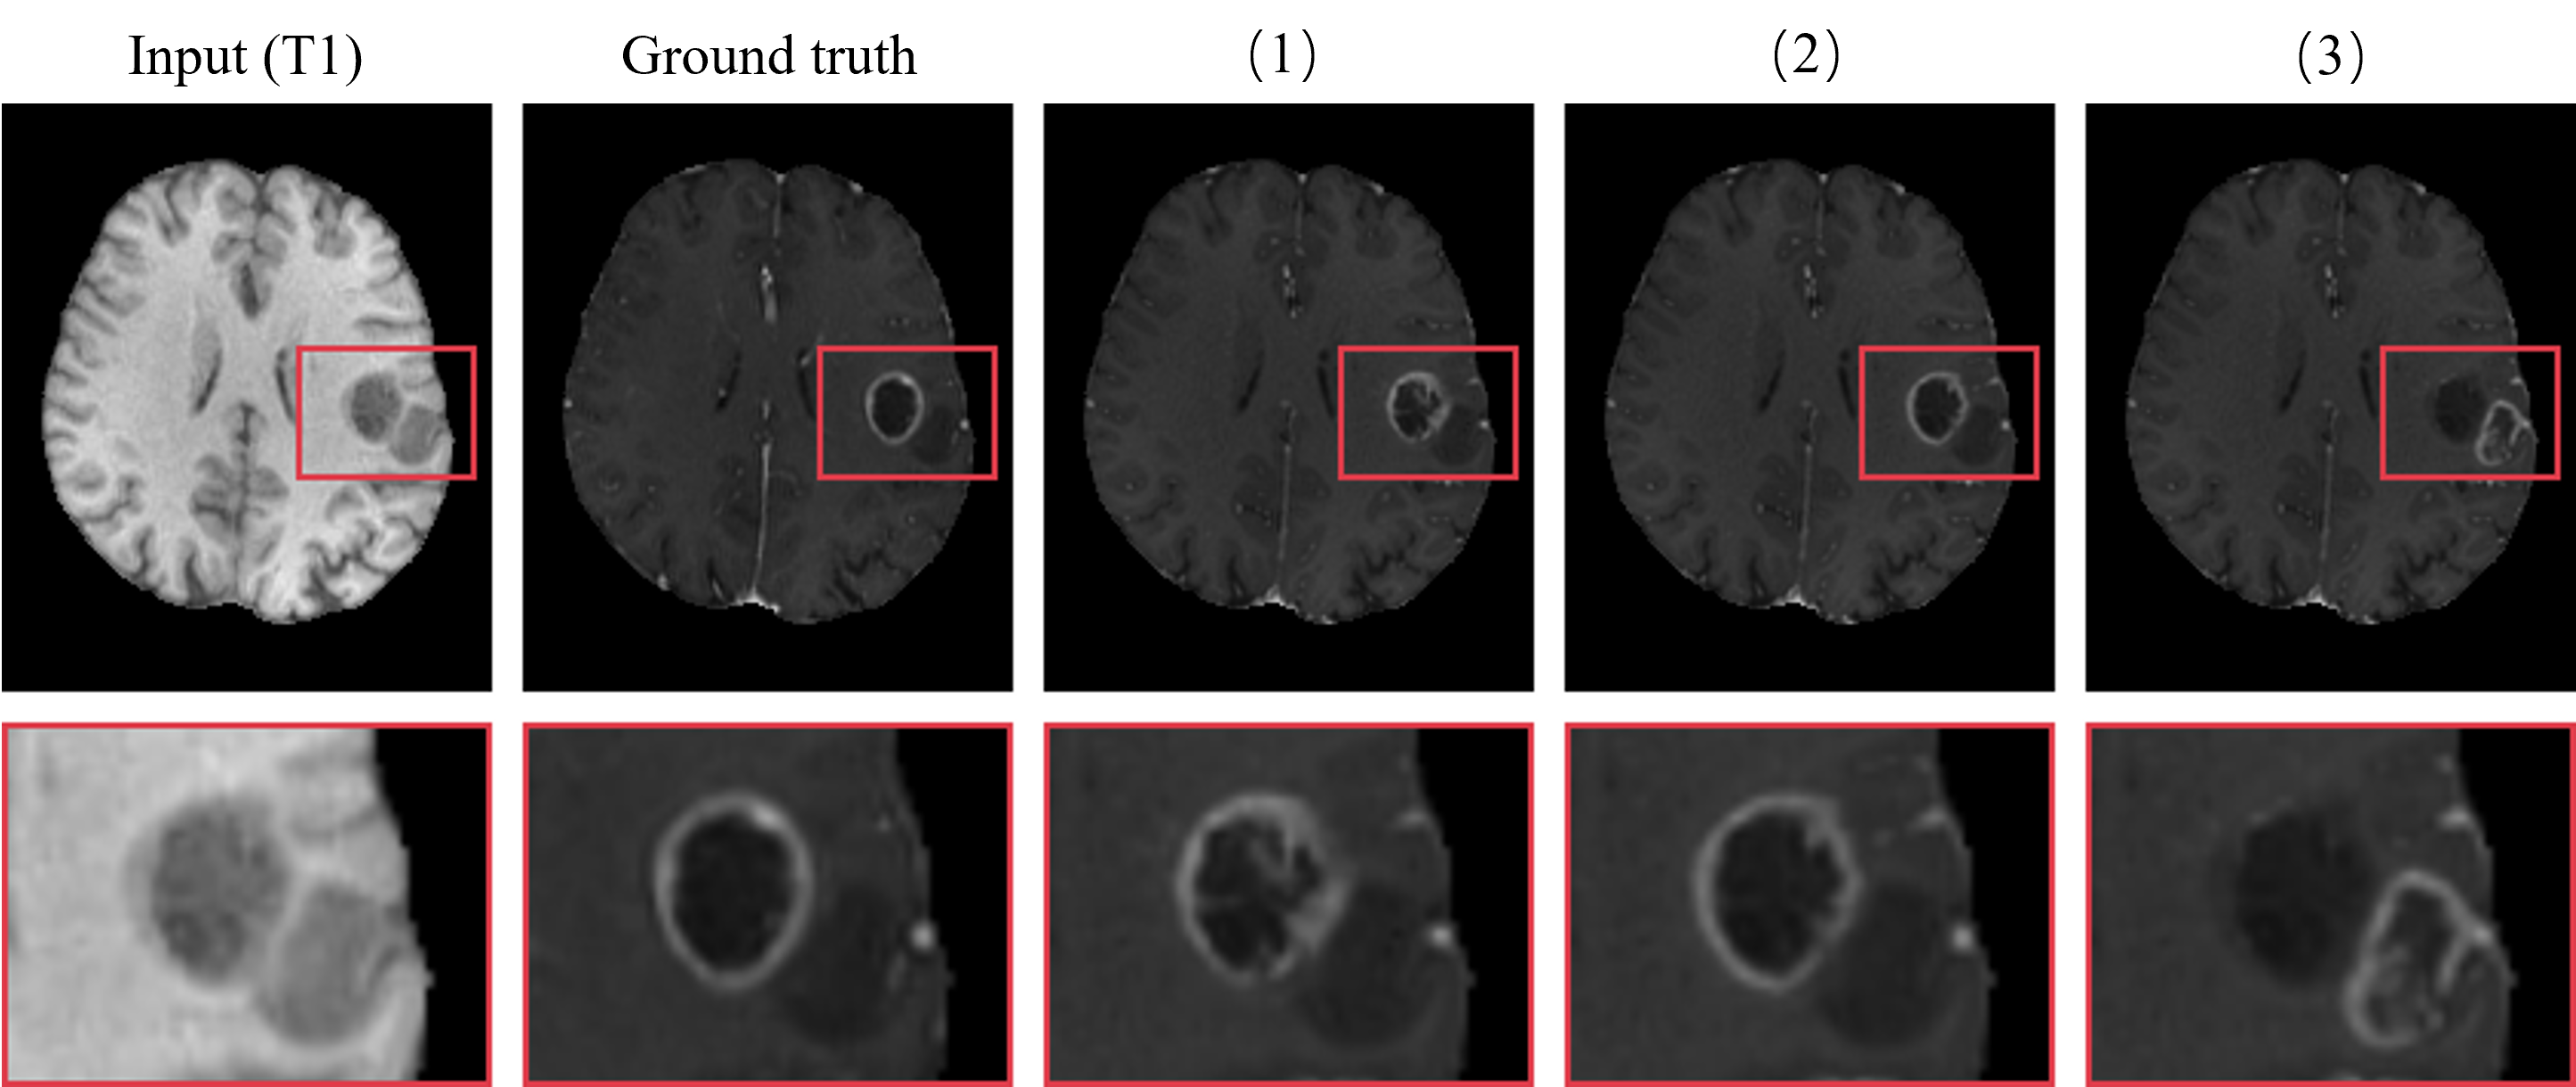

Refer to caption

Figure 6: Changing the prompt information can produce many interesting results. (1) is the image generated without any prompt, (2) is the image generated with the correct prompt, and (3) is the image generated with an intentionally incorrect prompt.

Additionally, an interactive model opens up intriguing research opportunities. In the case of the two elliptical shadows shown in Fig. 6, individuals without professional expertise might mistakenly identify both as tumors, when in fact only the inner shadow represents a tumor. Despite this, our model accurately enhance the tumor’s location without any prompts (see Fig.6-(1)). When the correct prompt is provided by circling the inner shadow, the generated result becomes significantly clearer (see Fig. 6-(2)). However, when another shadow region is circled as the prompt, the model produces an unclear, erroneous result (see Fig.6-(3), the quality of this erroneous result is clearly insufficient. This demonstrates that TLP offers better interpretability, enhancing our understanding of specific cases. Furthermore, the model’s ability to generate diverse results underscores TLP’s significant advantage in data augmentation for downstream tasks.